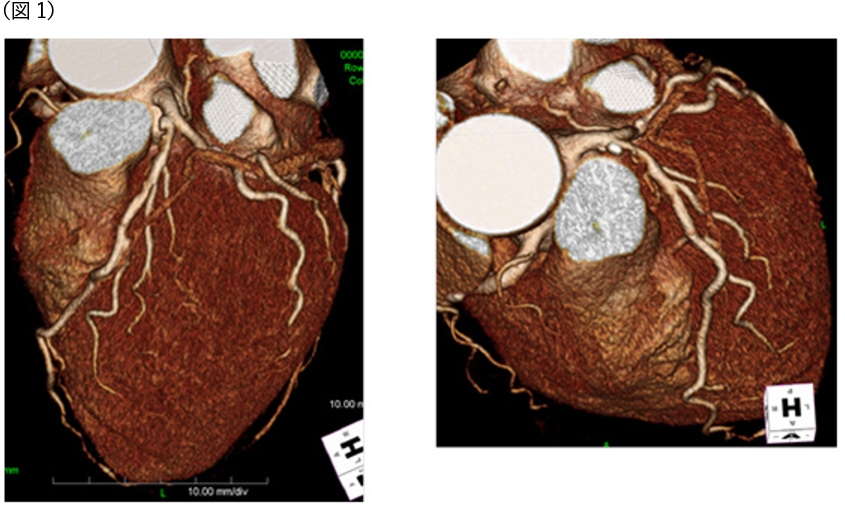

CT冠動脈造影実践学 | 木原康樹, 栗林幸夫 |本 | 通販 | Amazon, 冠動脈コンピュータ断層撮影装置(冠動脈CT),

冠動脈コンピュータ断層撮影装置(冠動脈CT), CT冠動脈バイパス術後解析 | 映像情報Medical,

CT冠動脈バイパス術後解析 | 映像情報Medical, 320列面検出器CTによる新しい冠動脈CT技術 吉岡邦浩(岩手医科,

320列面検出器CTによる新しい冠動脈CT技術 吉岡邦浩(岩手医科, 冠動脈疾患における CT-SPECT Fusion Imagingの有用性―ziosoft